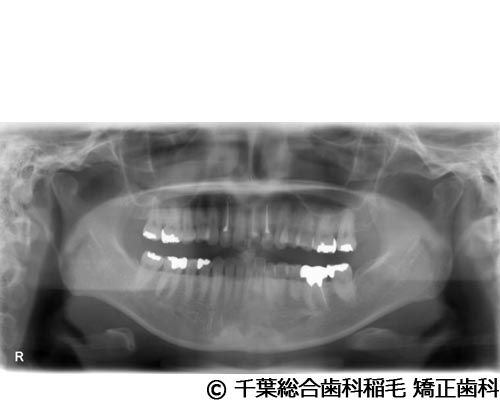

【症例3】上下5本インプラント埋入手術

- 治療前

- 治療後

- 治療名

- 上下5本インプラント埋入手術

- 費用

- 2,500,000円(税込)

- 期間

- 11ヵ月

治療内容

-

患者様の症状

欠損歯が多いため、お食事が取りにくく、インプラント治療のご相談でご来院されました。

治療法

状態の悪かった歯も含め、上下5本インプラントを埋入しました。

治療結果

奥歯でしっかり噛めるようになったと喜んでいただけました。

現在も定期健診で拝見させていただいています。